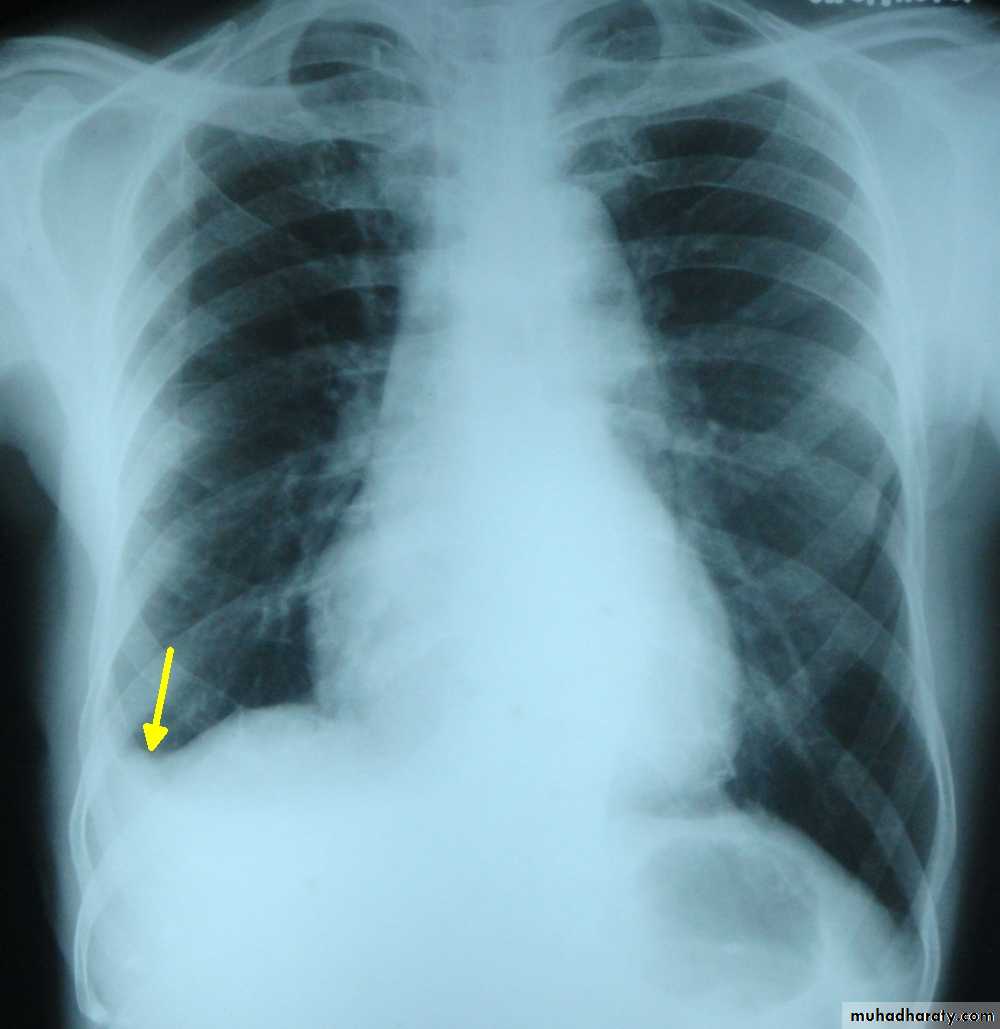

Chest x ray erect position, P-A view: blunting of the costophrenic angle on the right side, occurs once 200 ml of pleural fluid has accumulated.

A homogenous opacification is noted in the right lower zone with the opacity seen to track along the lateral chest wall. The right costophrenic angle is obliterated with a meniscus noted. Findings of a right sided pleural effusion.